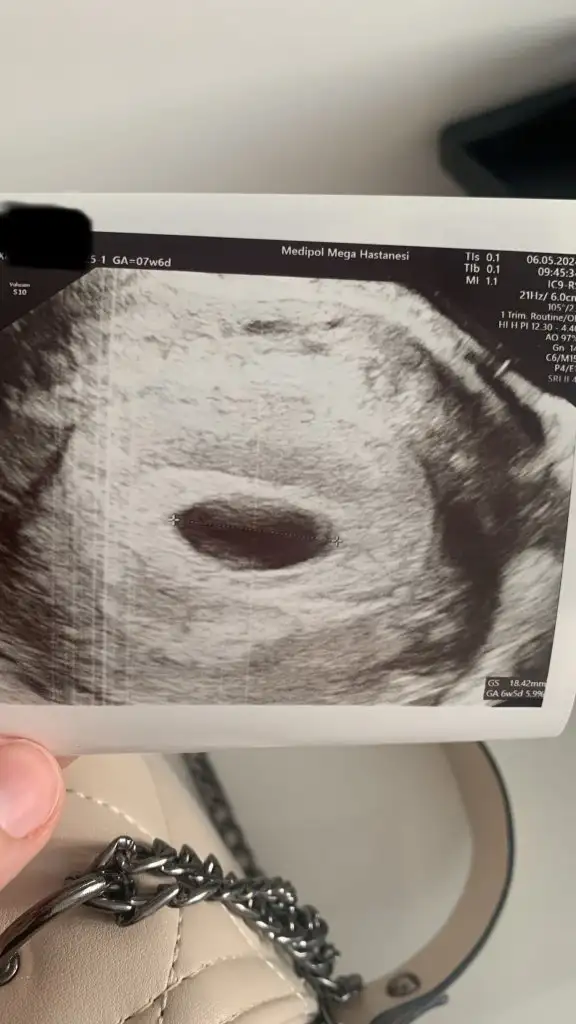

Nolur banada yardım edin . Ben bugün doktora gittim kese boyutu 18.42mm . Bebeği göremedi . Haftaya gel bebek yoksa kürtaj olucaksın dedi görseli ekliyorum. Başına gelen car mı??? 6+5 haftalık görünüyorKızlar selam yardımınıza ihtiyacım var.

Ben 6.haftada hamile olduğumu öğrendim. Beta hcg 19.000 bindi. Hemen doktora gittik, keseyi gördük. 9 mmdi.

6+6 da kontrole gittim kese 25 mm olmuş. Hcg değerim de 37.000 olmuş. Ama bebek ve kalp atışı yok. Ultrasonda kese fotoğraftaki gibi gorunuyor.

Kesede ufak bir şey gorunuyor ama doktor bişey demedi. Haftaya tekrar bakacağız dedi. Sizce burada bir şey var mı? Benimle benzer durumu yaşayıp bebeği sonra gören var mı? Boş gebelik olmasından dolayı endişe duydum. Hcg değerlerim normal mi?